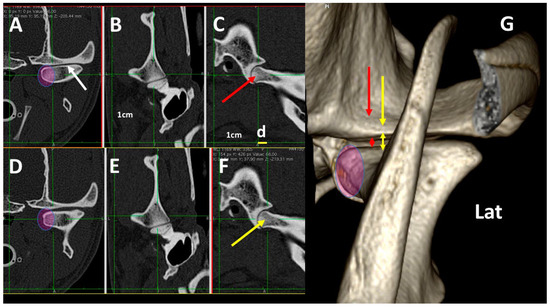

3.4. A Pictorial Essay of 3DVR Images in Some Pathological Cases